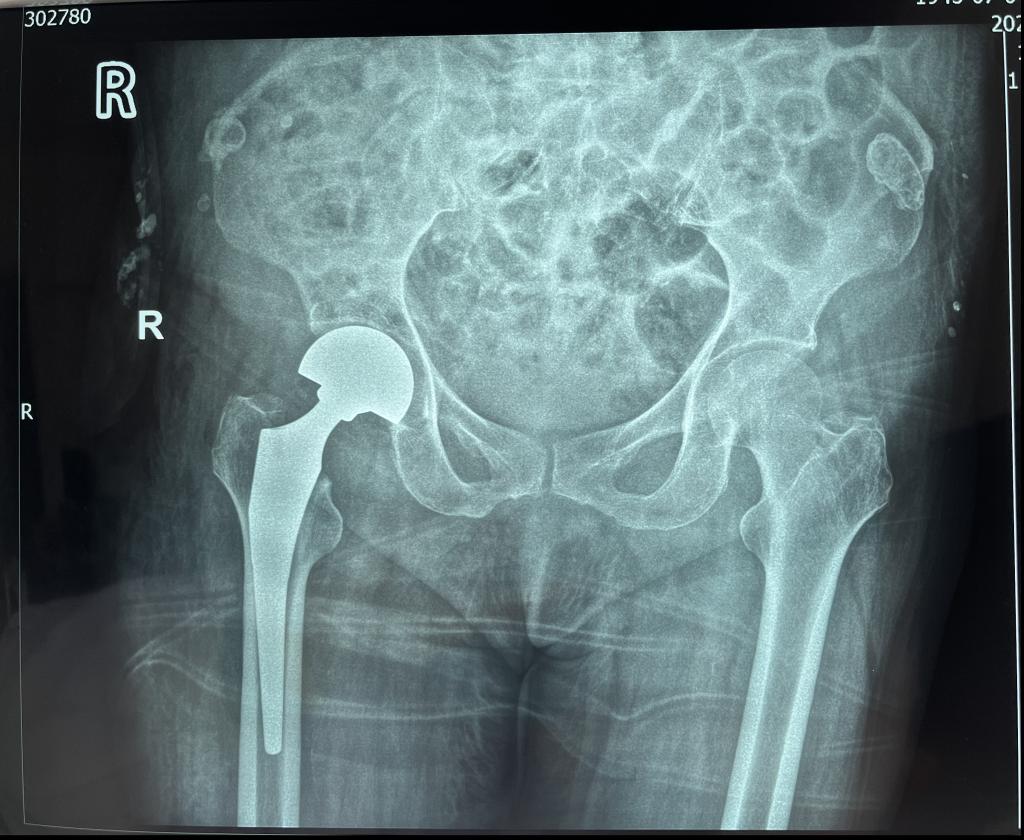

乐鱼在线登录入口骨三科暨骨关节科是以关节疾病为主,涉及关节病、运动医学及关节周围骨折、老年脆性骨折为亚专业特征的学科。科室针对因骨质疏松引起的老年股骨颈骨折、股骨转子间骨折、胸腰椎体压缩性骨折等已成功开展数百例老年髋部骨折绿色急诊手术通道、微创人工股骨头置换术、微创股骨骨折内固定术以及经皮椎体成形术,并取得不菲成绩。